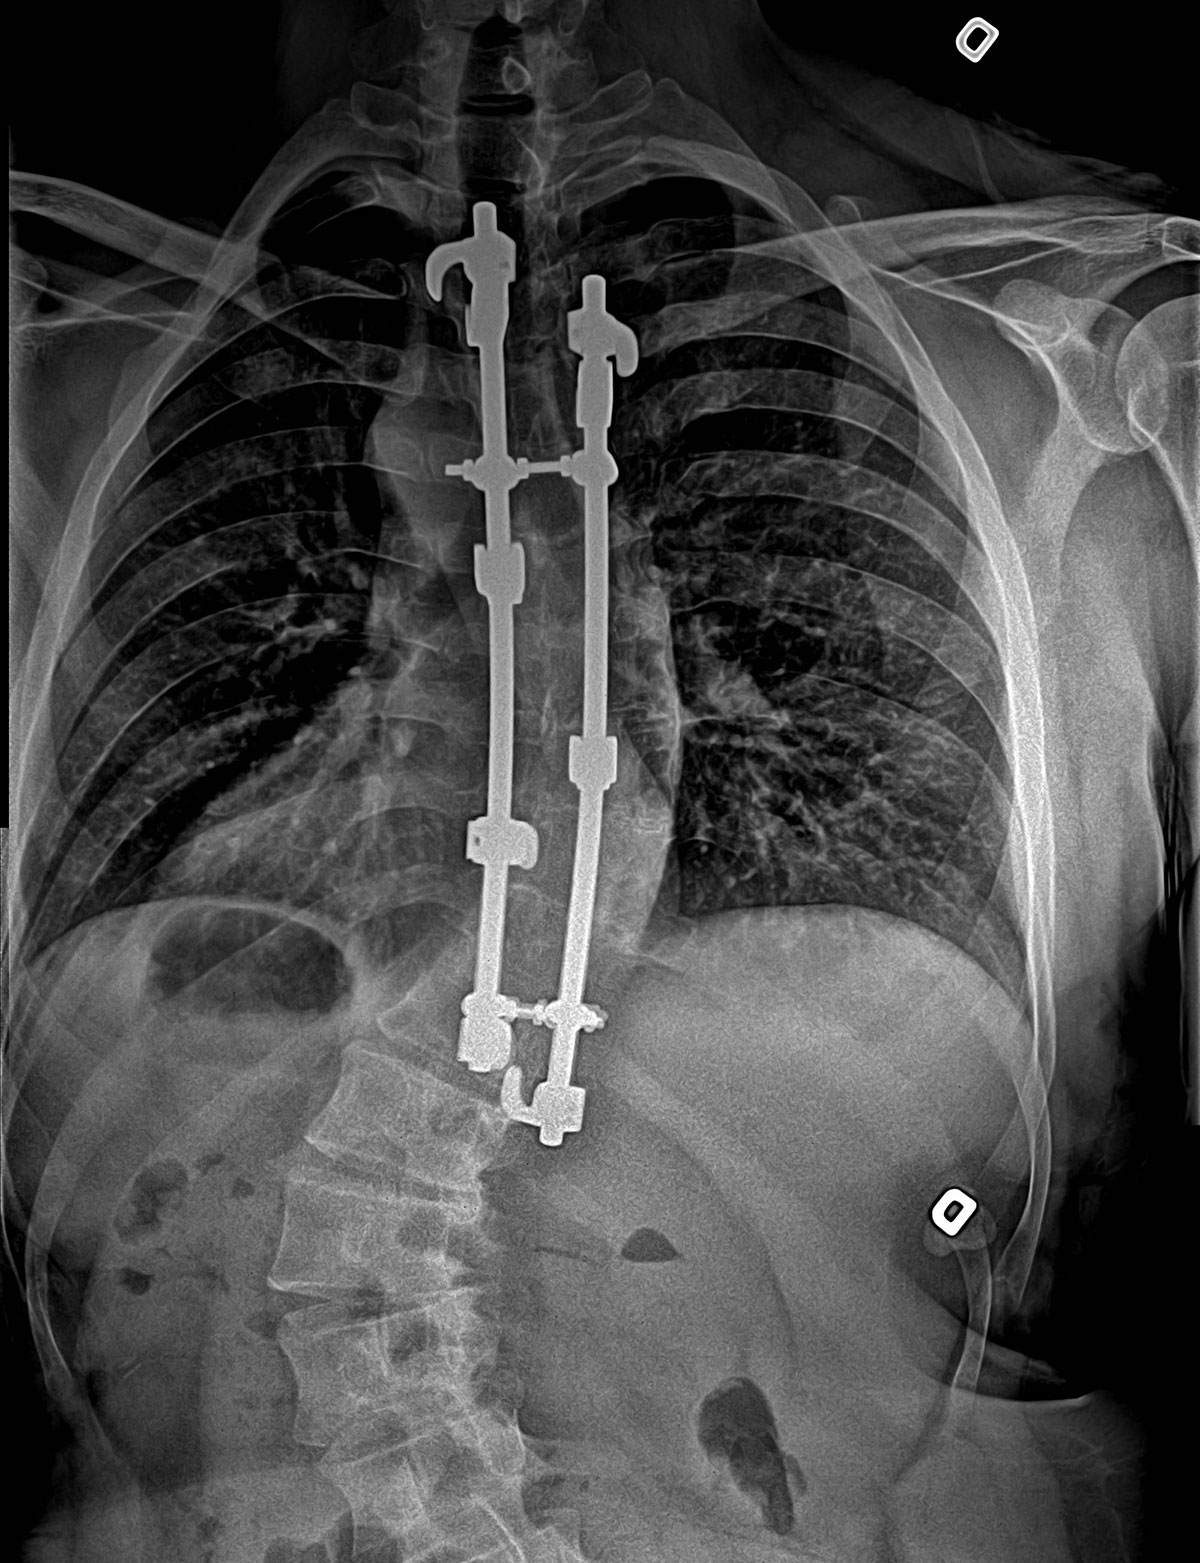

La chirurgie

Dans les cas graves et avancés de scoliose (courbes de plus de 50 ou 60°), on peut proposer au patient une intervention chirurgicale, la spondylodèse, qui consiste à fusionner des vertèbres à l’aide d’un pont rigide (os) et à stabiliser cette structure à l’aide de vis et de tiges de métal. Le but de cette intervention est avant tout de stopper la progression de la déviation.